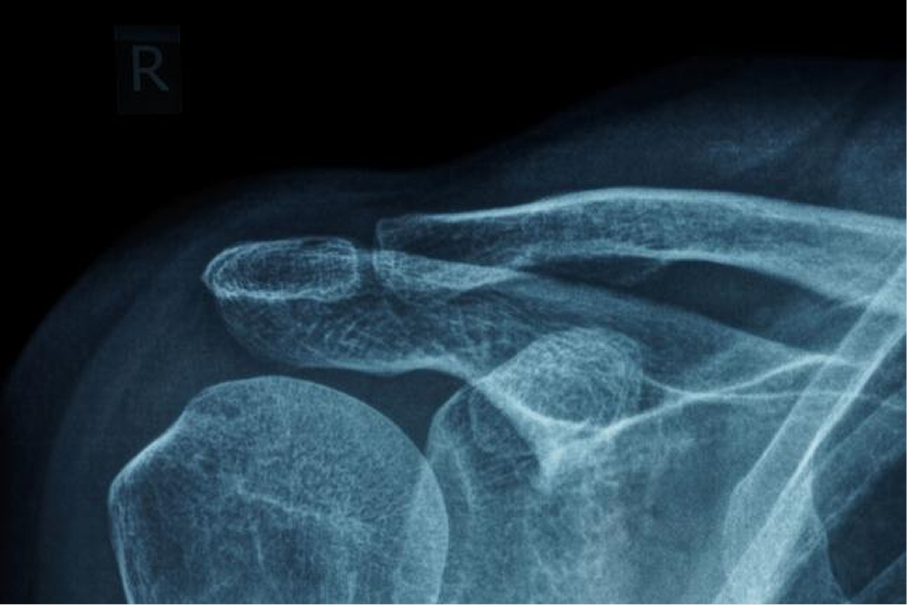

Radiograph

Radiographs are rarely useful in the absence of trauma. Plain shoulder radiographs are routinely obtained by an orthopedic surgeon during new outpatient visits, even in the absence of trauma. This wasteful practice continues despite the fact that most common diagnoses are soft tissue in nature and can be made through a physical examination. Counterproductive in many cases, they unduly lengthen a patient’s visit, expose a patient to unnecessary radiation, and add to the escalating cost of healthcare.